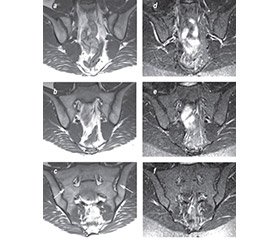

Рекомендації підкомітету ESSR щодо відповідних протоколів МРТ-сканування кісток таза для діагностики аксСпА охоплюють одночасну оцінку послідовностей T1-зваженого режиму (T1W) і режимів із пригніченням сигналу від жирової тканини: STIR-режим (інверсія-відновлення з коротким часом релаксації) і T2-FS-зважений режим із внутрішньовенним уведенням гадолінію або без такого (T1 w/wo FS post Gd) [9] (табл. 1; рис. 1). Губчаста речовина хребців, крижів і клубових кісток у нормі в дорослих містить жировий (жовтий) кістковий мозок, який може «перекривати» прояви запального набряку високим МР-сигналом, через що і необхідна технологія пригнічення МР-сигналу від жирової тканини кісткового мозку. Найкраще запальні зміни можна побачити у STIR-режимі, цей білий запальний сигнал контрастує з темним забарвленням кортикальної кістки і забезпечує добрий анатомічний поділ крижового і клубового кортикальних шарів ККС. T1W-режим на даний час є основним для виявлення кісткових ерозій за МРТ.

Жирова метаплазія

Жирова метаплазія виявляється при скануванні в T1W-режимі як яскравий білий сигнал у субхондральному кістковому мозку. Це ушкодження з’являється як еволюція НКМ і, зазвичай, розташовується поряд із субхондральною кісткою, з чіткою межею й однорідним білим сигналом по всій зоні ушкодження [21] (рис. 3a). Ця характерна ознака є високоспецифічною для аксСпА на відміну від гетерогенного розподілу білого сигналу, характерного для фізіологічної інфільтрації жиру в крижах [33]. Жирова метаплазія часто спостерігається разом з іншими структурними ушкодженнями в ККС при аксСпА [33].

Перша систематизована оцінка діагностичної цінності жирової метаплазії в діагностиці СпА була сфокусована тільки на наявності яскравого сигналу в T1W-режимі, а не на додаткових ознаках жирової метаплазії, таких як наявність вираженого кордону [17]. Наявність жирової метаплазії принаймні у двох секторах ККС була виявлена у 37 % пацієнтів із запальним болем у спині, але без рентгенографічного сакроілеїту, у 15,3 % здорових людей і 19,2 % пацієнтів із неспецифічним болем у спині [17]. У другому дослідженні й іншій когорті пацієнтів дослідники оцінили діагностичну цінність жирової метаплазії в поєднанні з іншими МРТ-ознаками для діагностики аксСпА [33]. Жирову метаплазію і наявність як мінімум двох різних ознак аксСпА було встановлено у 25 % пацієнтів із нерентгенографічним аксСпА, у 2,6 % пацієнтів із неспецифічним болем у спині та в жодного здорового суб’єкта. Аналогічним чином, в когорті SPACE у 23,5 % пацієнтів із діагнозом нерентгенографічного аксСпА відповідно до класифікаційних критеріїв ASAS і у 6,9 % пацієнтів без аксСпА спостерігалася жирова метаплазія при-

наймні в двох квадрантах ККС [34]. Крім того на відміну від НКМ тільки 10 % спортсменів мали жирову метаплазію в більше ніж двох секторах ККС [25]. Ці дані вказують на те, що жирова метаплазія має дискримінаційний потенціал і є ознакою, яка може бути корисною при контекстній інтерпретації МРТ-сканування для діагностичних цілей.

Кісткові ерозії

При скануванні в T1W-режимі ерозії кісткової тканини визначаються як повна втрата темного кортикального шару кісткової тканини, а також матриці сусіднього кісткового мозку [21] (рис. 3b). Ерозії виявляються як поодинокі або множинні кісткові дефекти суглобових поверхонь ККС. Велика ерозія визначається у вигляді локального розширення суглобової щілини. Ерозії мають гіпоінтенсивний МР-сигнал в Т1- і в STIR-режимах та часто поєднуються з субхондральним остеосклерозом і жировою метаплазією кісткового мозку. При активно запаленій ерозії яскравий сигнал також буде присутній у суглобовому просторі в режимі з пригніченням жиру, вказуючи на наявність запальної суглобової рідини.

Проспективні спостереження подемонстрували, що морфологія ерозій змінюється у міру зворотного розвитку запалення згідно з T1W-скануванням ККС [36]. Зокрема, яскравий сигнал при скануванні у STIR-режимі зникає і з’являється посилений сигнал в суглобовому просторі на місці ерозивної порожнини при скануванні в T1W-режимі (рис. 3c і 4). Вважається, що ці зміни відображають репаративний процес в місці ерозії, що нагадує трансформацію НКМ у жирову метаплазію в субхондральній кістковій тканині. Цей репаративний процес відновлення ушкодження в місці ерозії був названий зворотним засипанням для позначення заповнення ерозивної порожнини новою тканиною, хоча також був недавно запропонований інший термін — «жирова метаплазія в ерозивній порожнині» [21]. Дані плацебо-контрольованого рандомізованого дослідження показують, що цей процес відбувається вже через 12 тижнів після початку лікування інгібітором фактора некрозу пухлин [37].